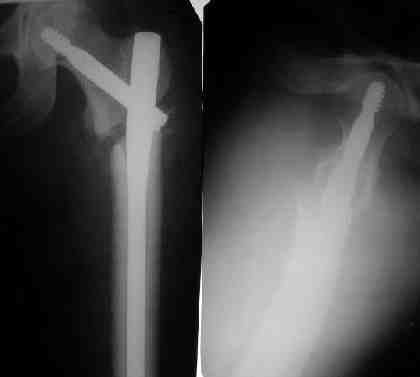

Могу скромно напомнить о существовании стержня нашей модификации.

В частности, на проксимальном конце сделано еще одно дополнительное статическое отверстие. Можно ввести в проксимальном отделе 4 винта, из них 3 статические (2 в круглые отверстия и 1 по нижнему краю овального). Картинки в приложении. На дистальном конце стержня тоже кое-что улучшено. Спрашивайте в аптеках, как говорится. Выпускается предприятием "ЦИТО" (Москва), то есть это малобюджетное решение.

Конечно, мы не синтезируем остеопорозые вертельные переломы согласно прилагаемому примеру, винты 6 мм вырежутся. Но у более молодых при хорошем качестве кости такие или подобные гвозди с поперечным расположением винтов вполне применимы для меж- и подвертельных переломов.